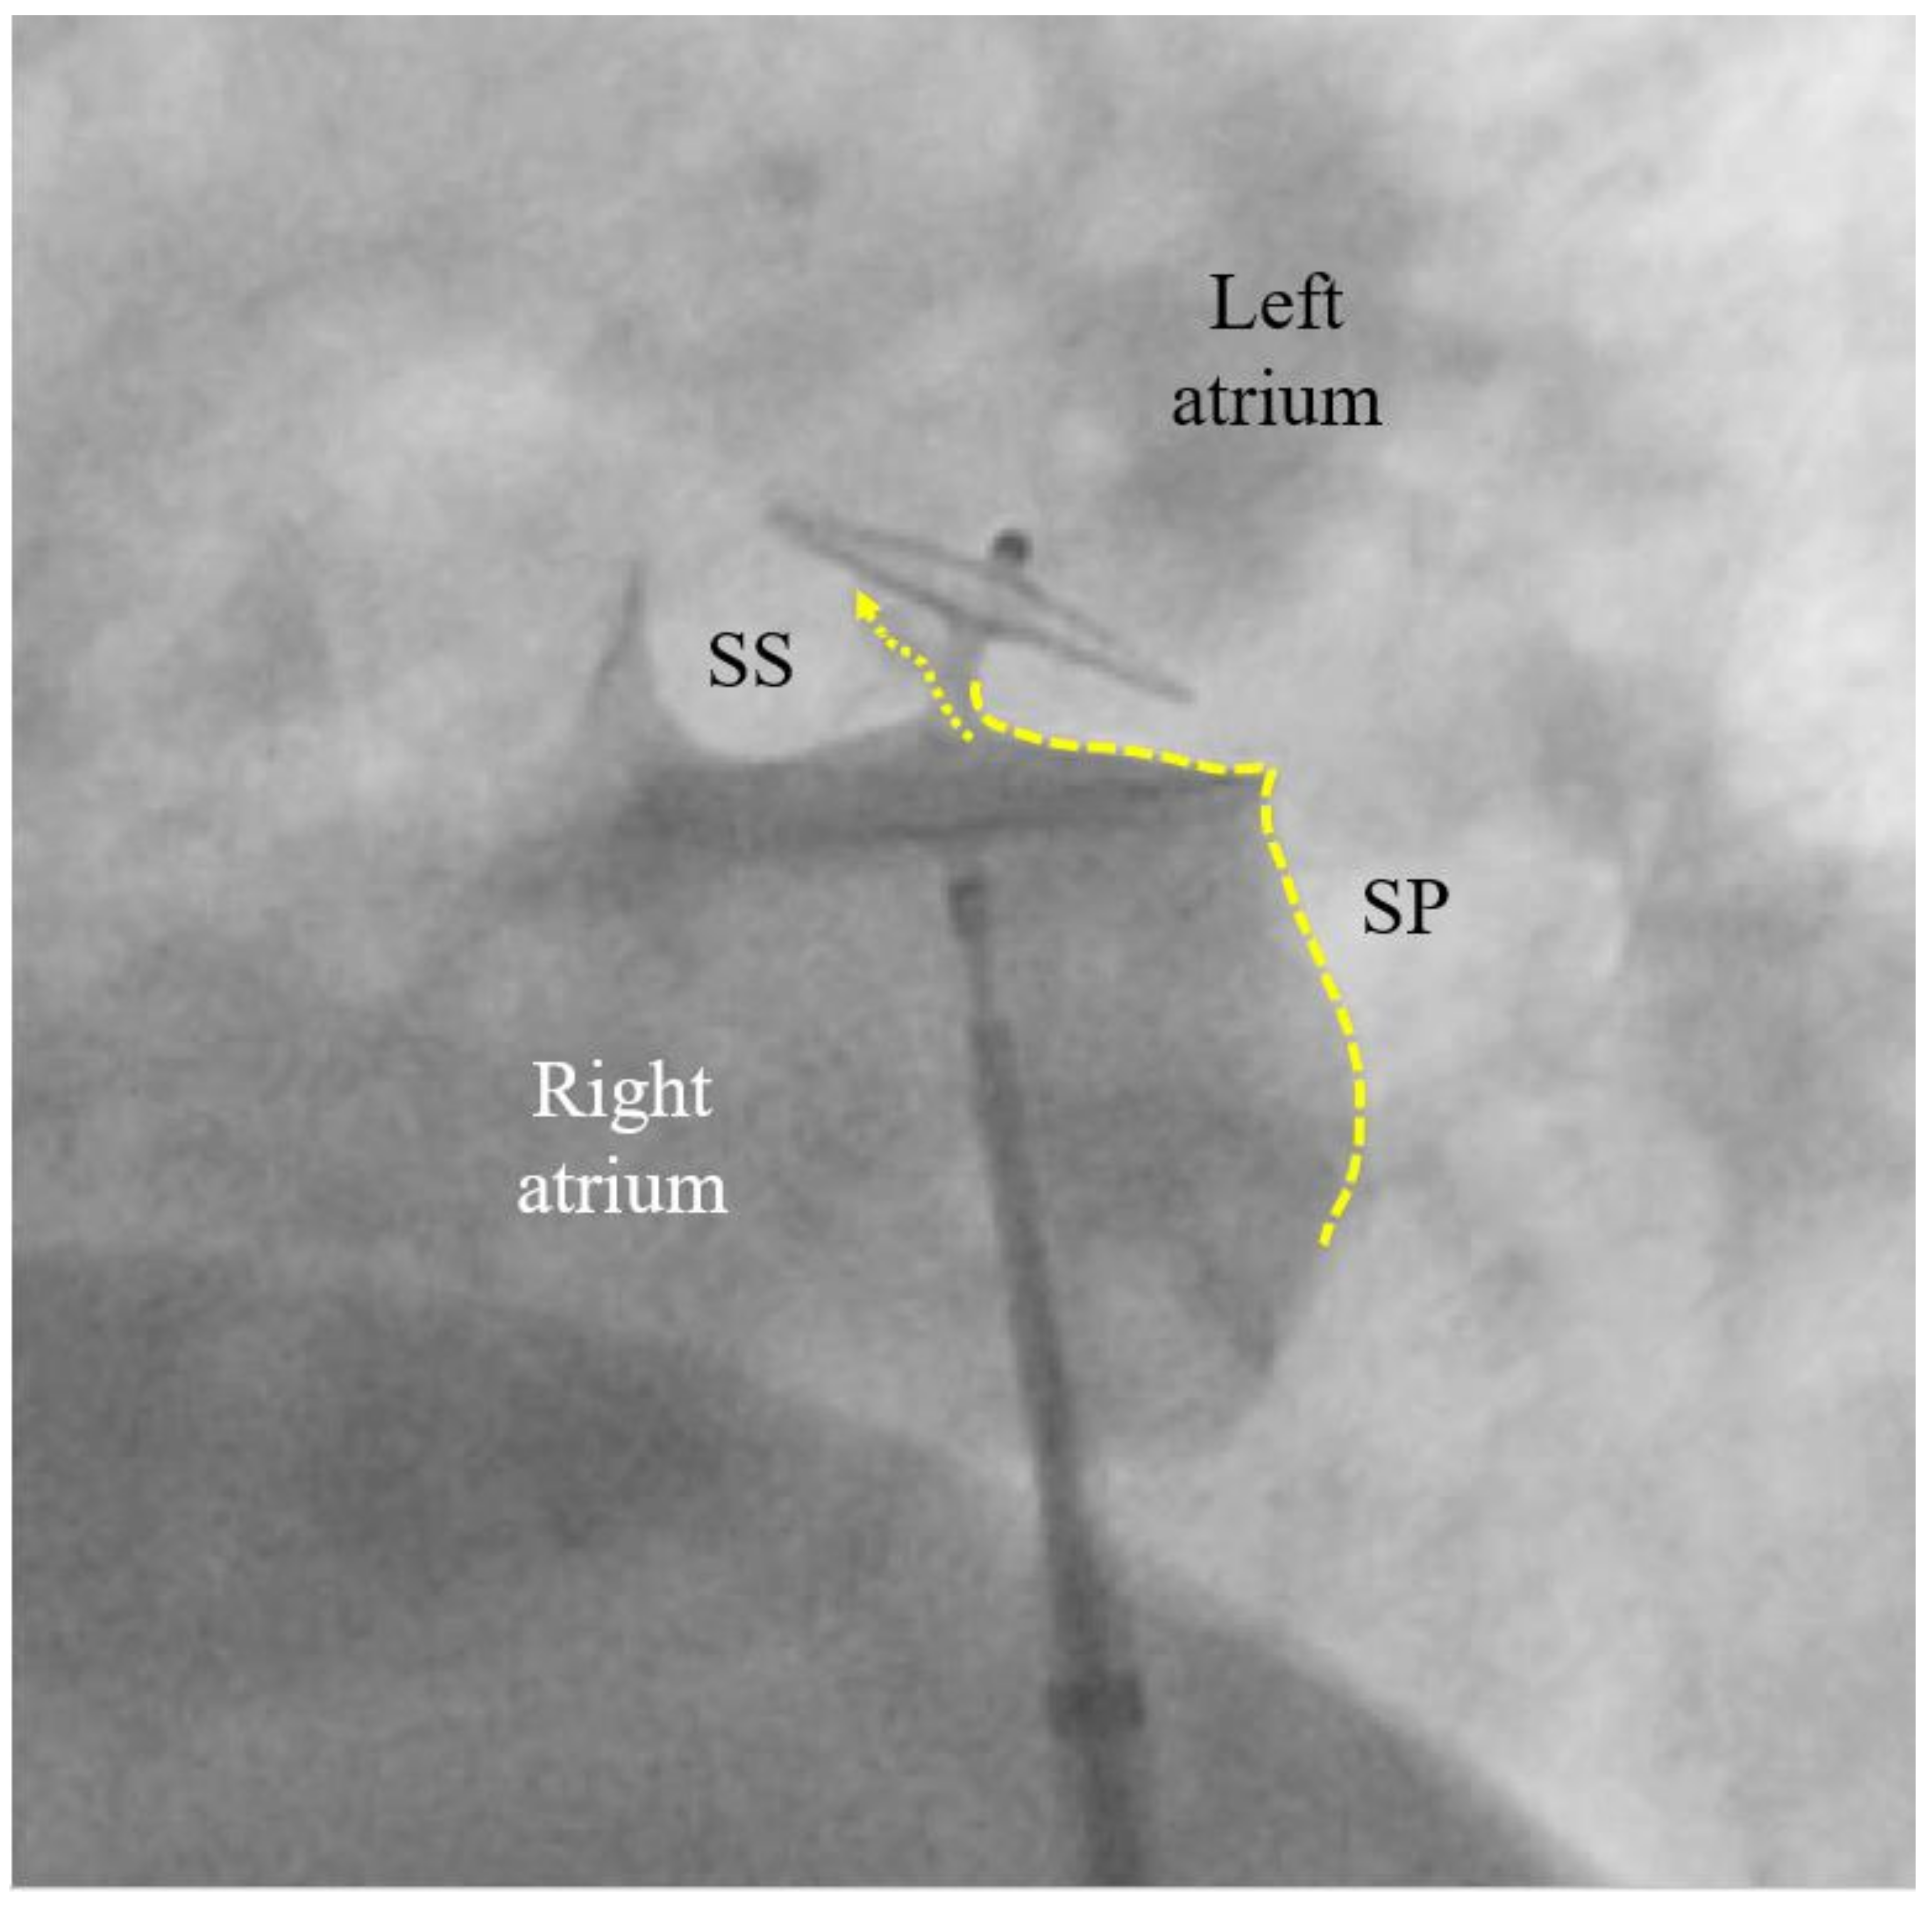

If the PFO cannot be passed despite changing direction and position of the multipurpose catheter, the U-tip wire may be removed and the tip straightened by scratching the back of the curve with the thumb nail. Should the now straight wire still not pass, the PFO is searched for with the tip of the multipurpose catheter. If even that fails, a right atriogram with contrast medium is performed to understand the anatomy (Figure 1). The initial attempt to pass the atrial septum with a U-tip wire tries to take advantage of the fact that the U-tip wire can only pass through the slit-like PFO. A straight wire or a catheter may inadvertently pass through a tiny atrial septal defect (ASD) in the septum primum. Small cribriform ASDs often go unnoticed in prior echocardiograms.

A contrast medium injection is done after flushing the sheath and after adjusting the projection so that both discs are seen in perfect profile without any overlap. It will show all necessary details (Figure 3). The device is then released, i.e., unscrewed from the pusher cable or liberated by whatever attachment and release mechanism is used with alternative occluders. A further contrast medium injection after readjusting the projection is required only if the device moves significantly upon release. This typically happens in the presence of an atrial septal aneurysm (ASA) or due to significant position distortion by sheath or pusher gear before release (Figure 3).

The left (cranial) part of the 25/18 mm Amplatzer PFO Occluder is correctly biting into the septum secundum (SS). That is called a positive Pacman sign and is required for safe release. The original channel of the PFO is now blocked (dotted arrow). The septum primum (SP) is indicated with a dotted line. Its part caudal to the occluder is ideal for possibly later requiredfluoroscopy-guided transseptal punctures. A pre-release situation like this will usually have the device swivel up to a quarter turn clockwise upon release. The final occluder position is expected more vertical and parallel to the atrial septum with no more dent in the SP.

MI. MI by paradoxical embolism through a PFO must be one of the most frequently misdiagnosed problems in cardiology.50 This is particularly vexing because it is easily preventable by PFO closure. The cardiologists are the ones to blame for this oversight. In the wake of the bad example of neurologists who for nebulous reasons want to have excluded all other potential causes for stroke before scouting for a PFO, cardiologists think of all imaginable causes for a MI before considering paradoxical embolism. In the absence of obvious atherosclerosis (the prime suspect), spontaneous coronary dissection, protracted spasm, or drug abuse are pondered, searched for, or incriminated right off the bat, but not a PFO. The mentioned fact goes ignored that atherosclerosis, age, and systemic disorders promote rather than exclude paradoxical embolism of a venous clot. Only a minority of interventional cardiologists list a PFO among the acknowledged causes for MI. The amount of blood supply per minute to the coronary arteries is about 220 ml/minute at rest. This corresponds to almost a third of that to the brain (roughly 750 ml/minute). Both organs are equally jeopardized by the small clots typically passing through a PFO. Limbs and visceral organs require larger clots for serious ischemic harm. In brain and heart, there are silent embolisms thanks to unimportant areas, pre-existing tissue scars, or collateralized territories. Accounting for all that, one should attribute to a PFO roughly one MI per three cerebral events. This has yet to take into account that neurology significantly underdiagnoses PFO mediated cerebral events. Typically, they are ruled out by default in patients with the highest respective risk. The number of correctly diagnosed PFO mediated MIs should probably be at least hundredfold higher than it currently is. Any acute MI looking even remotely embolic, should prompt a search for a PFO, once the coronary situation is managed. This can be accomplished with a right heart catheterization at the end of the primary coronary percutaneous intervention. Rather than directly probing the PFO with a wire or a catheter as described above, a right atrial injection is preferable (Figure 1). There is a small but concerning risk of a thrombus saddling the PFO,24 part of which just broke off and caused the acute MI. Excluding or proving and closing a PFO in that way adds a few minutes to the coronary case and is doable day or night. It does not really increase the overall risk of the procedure but can do a lot of good. It makes sense in embolic looking MIs irrespective of whether or not they were indeed caused by the PFO. The next MI could well be and a mechanical vaccination against paradoxical embolism is never unwarranted. By the way, screening for a PFO with a right heart catheter is less uncomfortable for the patient than with a TEE. The characteristics of the PFO needed to select the appropriate device size (Figure 4) can be equally well depicted with such a contrast medium study (Figure 1). A combined coronary intervention and PFO closure is in the vetted interest of patients.

Figure 3. Contrast medium injection before release of a patent foramen ovale (PFO) occluder (left anterior oblique view).

Figure 4. Device size selection for closure of a patent foramen ovale (PFO) made simple. The length of the tunnel is not relevant. ASA = atrial septal aneurysm; SP = septum primum; SS = septum secundum.